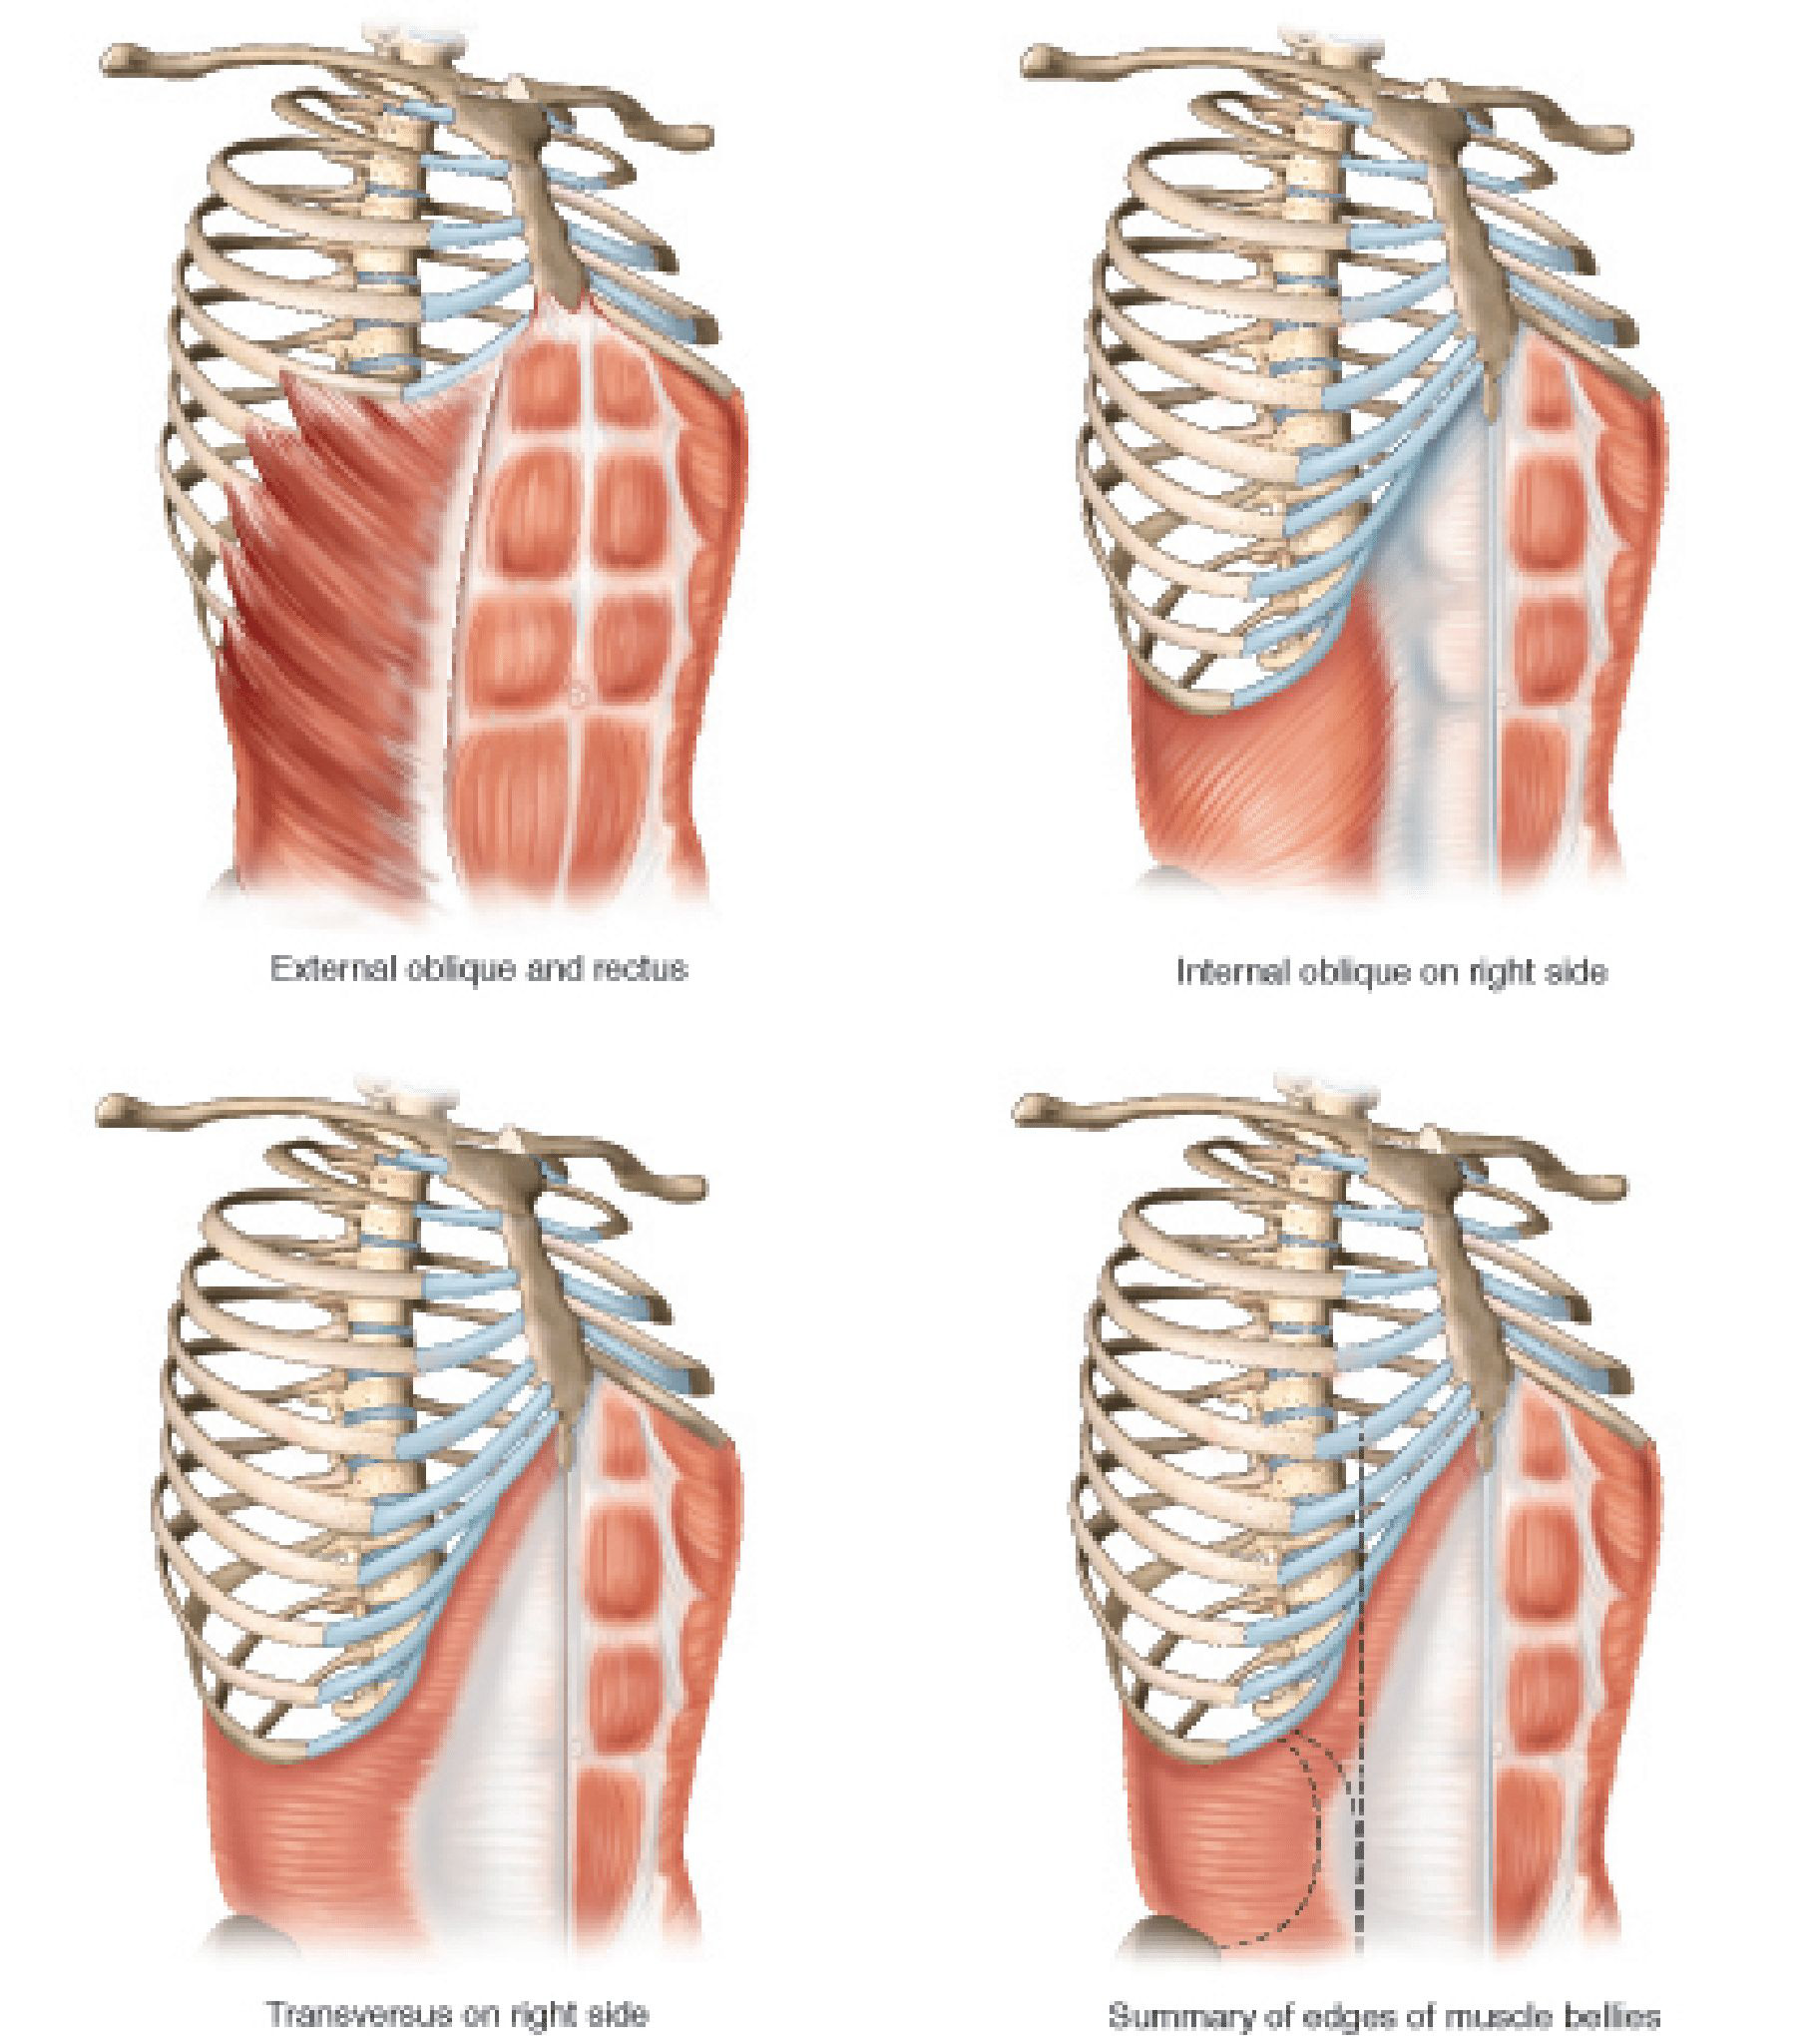

I am a medical illustrator! I wanted to be a doctor and was enrolled in premed, then received a few flyers for colleges in the mail for medical illustration. I decided to change my major from premed to medical illustration. I studied at two private colleges in a combined program for art and medicine.

I create medical illustrations, animations, interactive projects and timelines for physicians, attorneys, medical device and pharmaceutical companies to create illustrations for educational purposes.

I am proud to educate people. To scientifically visualize what’s unseen by the naked eye for the general public!

Image Credits

Lindsay Coulter